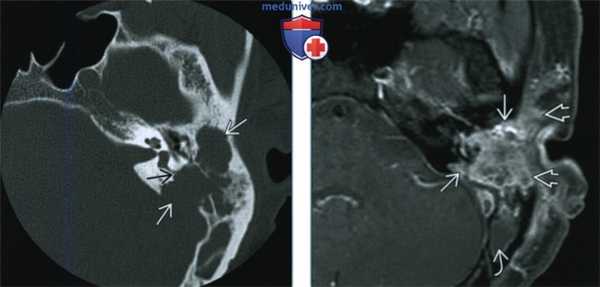

(Слева) При аксиальной КТ в костном окне определяется четко очерченный литический очаг деструкции в левой височной кости, обусловленный ЛКГ, с поражением слуховой капсулы (которая редко подвергается эрозии в большинстве ситуаций).

(Справа) При аксиальной МРТ Т1 С+ FS определяется распространенное контрастирование левой височной кости вследствие поражения ЛКГ с вовлечением окружающих экстракраниальных мягких тканей. Обратите внимание на «запертую» жидкость в задних отделах сосцевидного отростка.